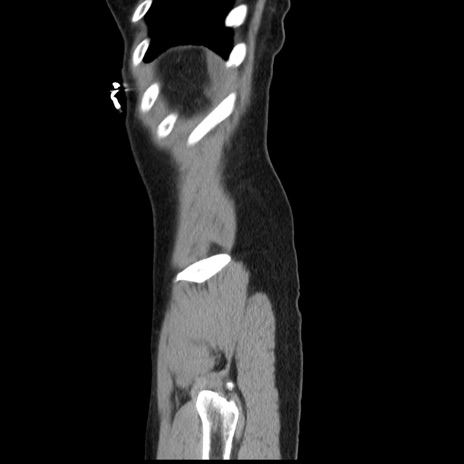

横断像